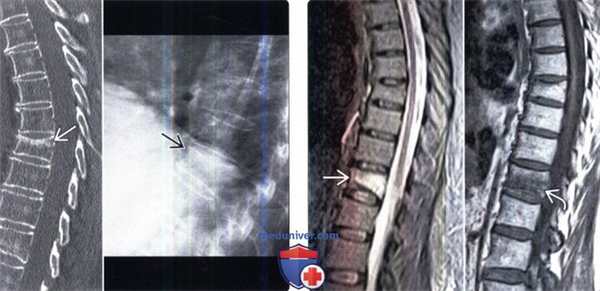

(Слева) На сагиттальном КТ-срезе и рентгенограмме в боковой проекции визуализируется остеопоротический перелом тела среднегрудного позвонка.

(Справа) На сагиттальном STIR МР-И отмечается гиперинтенсивность сигнала тела среднегрудного позвонка, связанная с отеком костного мозга на фоне свежего остеопоротического компрессионного перелома. На Т1-ВИ определяется гипоинтенсивность сигнала и низкоинтенсивная полоса, представляющая собой линию перелома. Негомогенная ИС в Т1/Т2/STIR-режимах и неполное замещение костного мозга являются характерными признаками доброкачественного характера перелома.